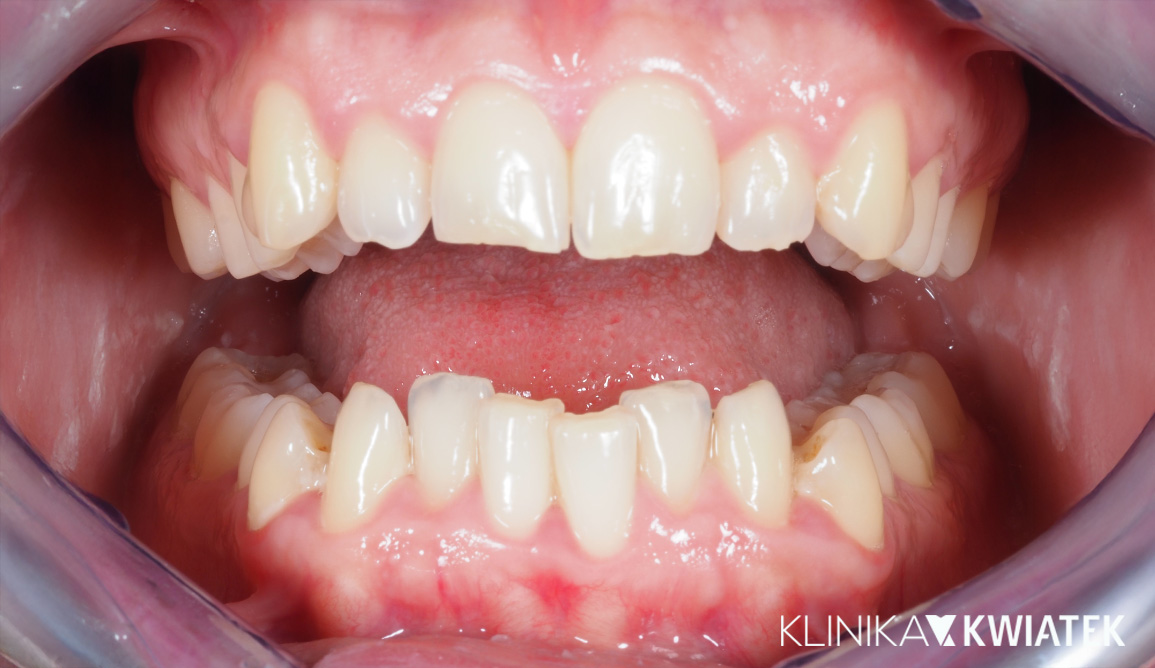

Kompleksowe leczenie i odbudowa funkcji – droga do pięknego uśmiechu

Do naszej Kliniki zgłosił się Pacjent z poważnymi problemami stomatologicznymi – licznymi ubytkami, nieprawidłowym zgryzem oraz widocznym starciem zębów, co wpływało na estetykę i funkcję. Przeprowadziliśmy kompleksowy plan leczenia: od diagnostyki, higienizacji i leczenia zachowawczego, przez szynoterapię i leczenie implantologiczne, aż po pełną odbudowę protetyczną. Efekt końcowy to zdrowy, harmonijny uśmiech oraz pełny komfort w codziennym funkcjonowaniu.